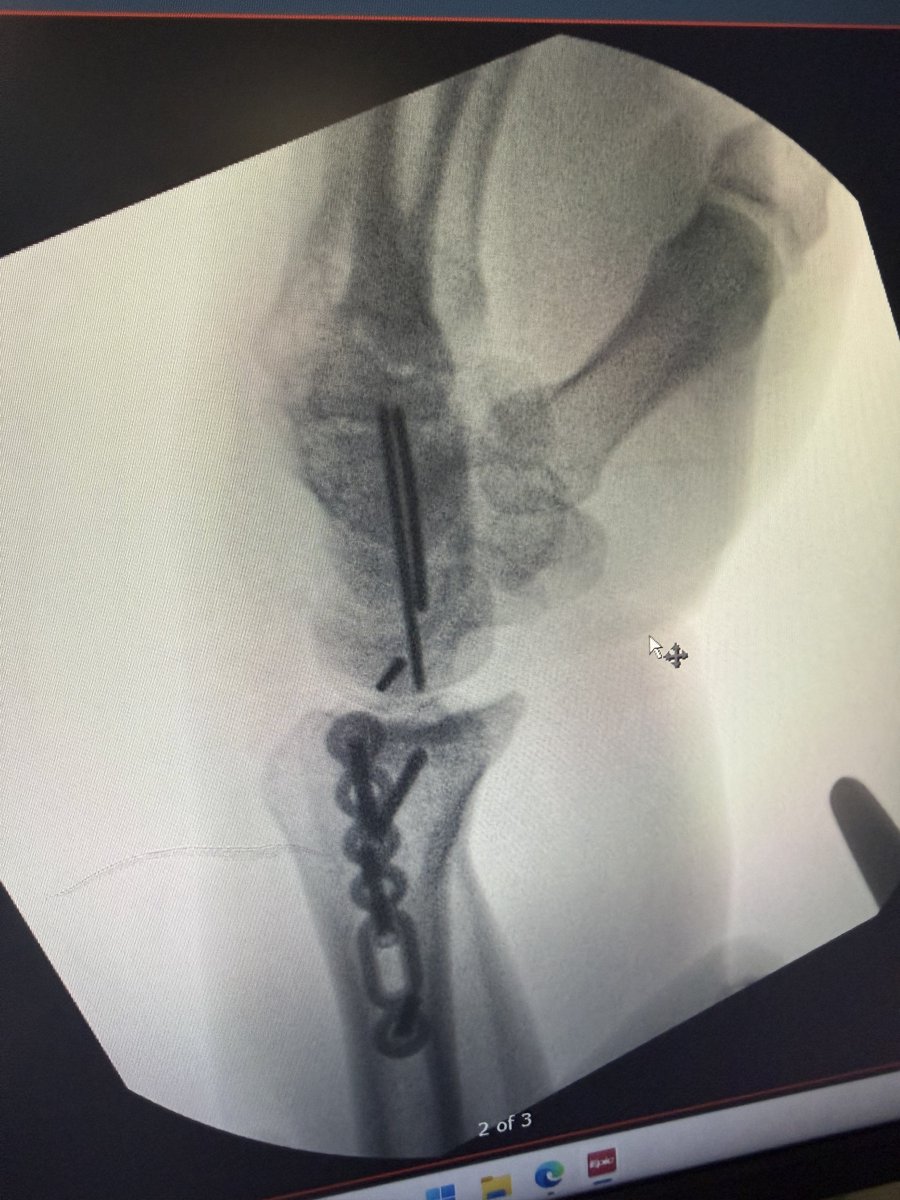

@RMexico11 So it was dislocated as well but they got all the bones and stuff back in place a little while ago and I will do surgery in the morning to add some pin screws plates